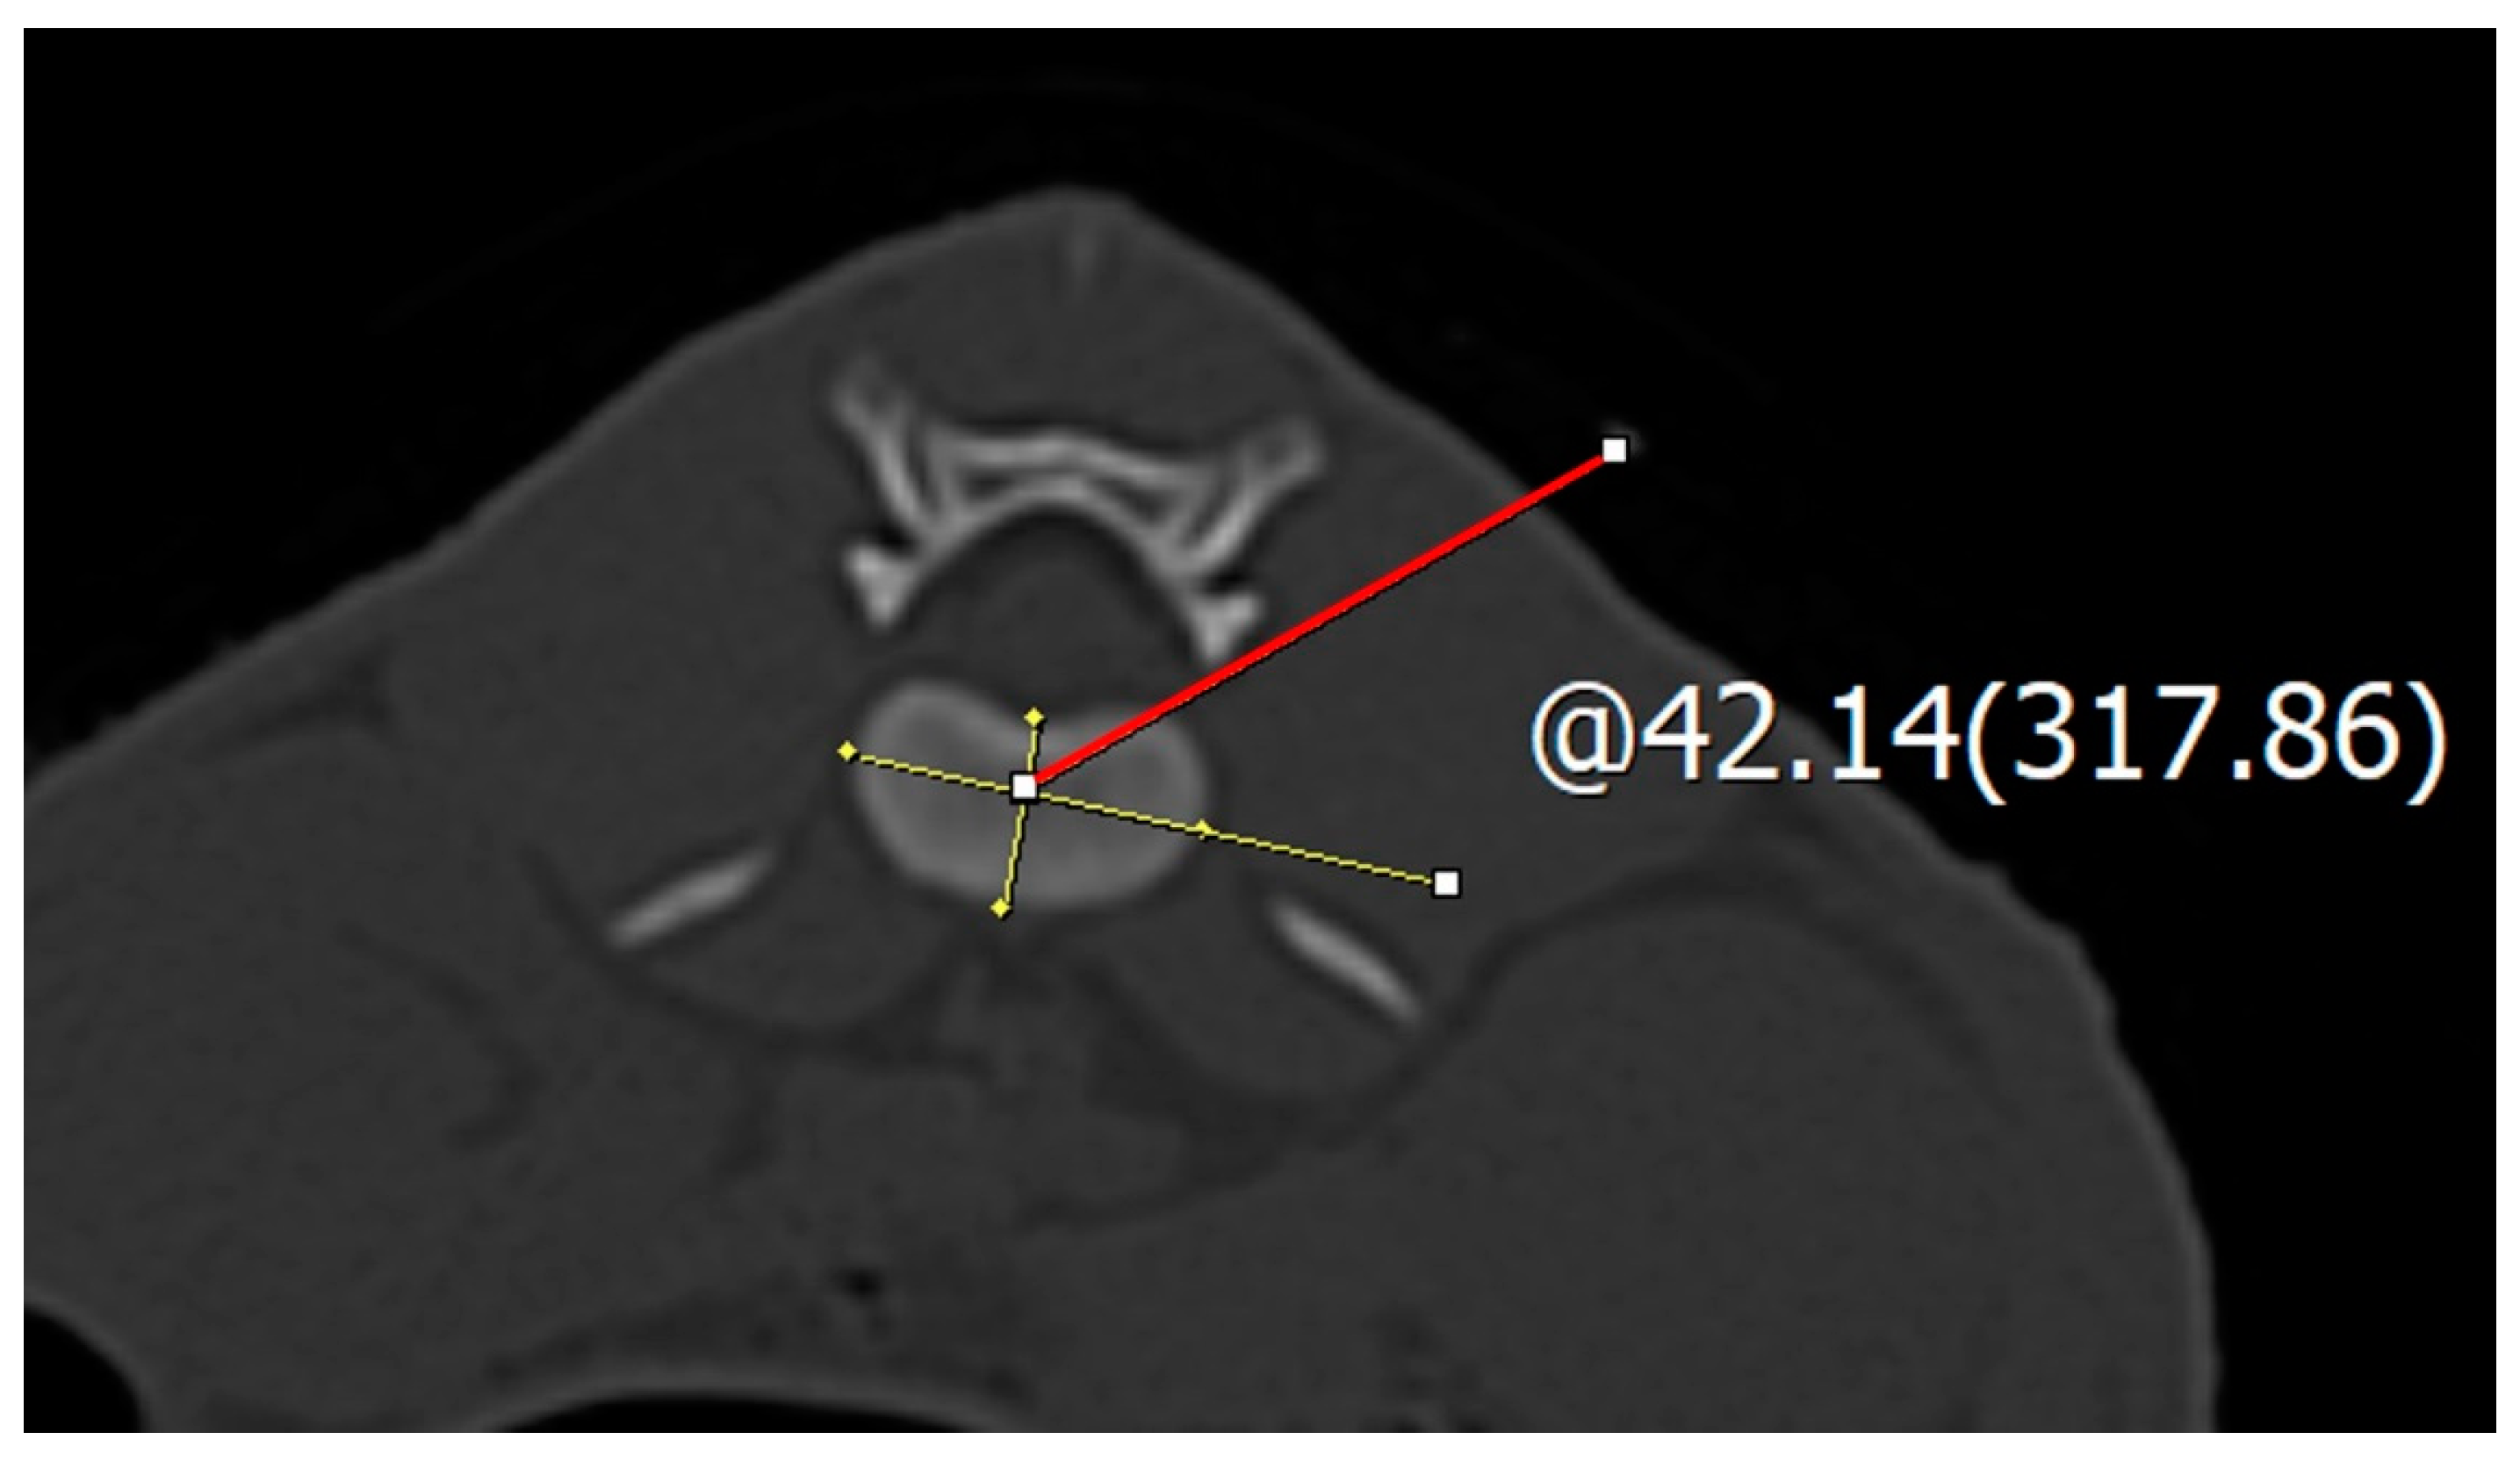

2.2. Spinal Needle Safe Corridor Evaluation

2.3. Safe Corridor Evaluation at the Thoracic Region

2.4. Safe Corridor Evaluation at the Lumbar Region

3.1. Safe Corridor Angle at the Thoracolumbar Region